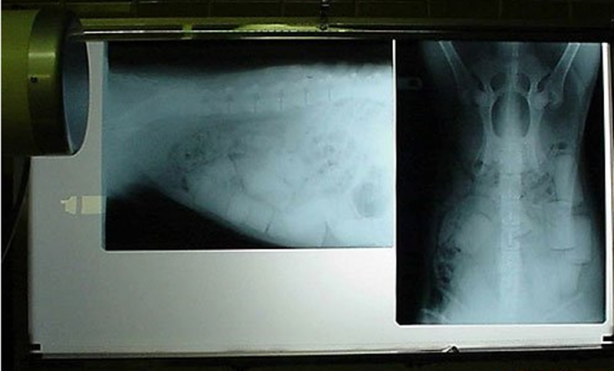

Hamile bir kedi ve onun röntgen filmi.